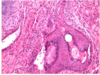

ectoderm teratoma

squamous epithelium

hair follicles

mesoderm teratoma

cartilage surrounded by metabolically active spindle cells

GI epithelium

endoderm teratoma

classification of teratomas

- Divided into mature and immature

- Mature – mature tissue

- mature either solid or cystic (ie dermoid cyst)

- can become malignant – any type of tumour because any type of tissue can be present

- Immature – embryonic or fetal tissue – bad prognosis - because the tissue can proliferate because have the stem cells

- Also contain mixed elements

can be monodermal - ie one layer